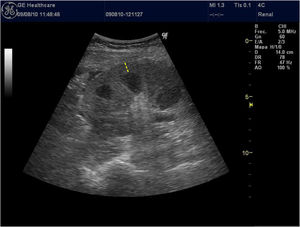

Grosor parenquimatoso, grosor cortical y ancho renalExiste correlación del grosor parenquimatoso con el grado de ERC mejorando estadísticamente esta asociación si se corrige por altura corporal1. Se ha asociado inversamente con el grado de atrofia tubular. Sin embargo, no es así con el espesor cortical11 (fig. 1).

El espesor parenquimatoso corregido fue el único parámetro de modo B (excluido la ecogenicidad parenquimatosa) que se redujo de forma progresiva conforme disminuía el FGe. Este parámetro demostró tener mayor especificidad según la curva ROC para distinguir un FGe inferior a 60mL/min comparado con las curvas ROC de la longitud, cortical y ancho renal. Sin embargo, presentó un área bajo la curva (AUC) inferior en comparación con la ecogenicidad del parénquima renal1,12.

El parámetro del grosor de la corteza renal es poco utilizado por los investigadores por la dificultad de medición en pacientes con mala diferenciación coticomedular, hallazgo que se observa más frecuentemente en paciente con ERC avanzada. Al presentar una interfaz difícil de identificar, la reproductibilidad es baja, por este motivo pocos estudios lo utilizan y esto se traduce en que no haya datos consistentes acerca de la asociación de grosor de la corteza renal y deterioro de función renal. Asimismo, Beland et al.13 demostraron que el grosor de la cortical estaba estrechamente correlacionado con el FGe (fig. 2).